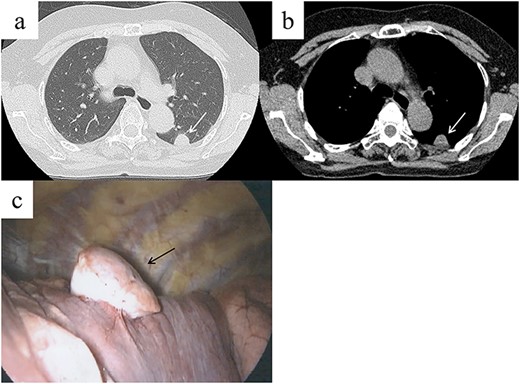

A 62-year-old female visited our hospital because of an abnormality that was detected on a chest radiograph during a routine health screening. The patient was a nonsmoker and was asymptomatic. She had undergone surgery for papillary thyroid cancer 5 years prior. Physical examination and laboratory test results were normal. Chest CT revealed a 22-mm well-demarcated solid nodule in the lower lobe of the left lung, adjacent to the pleura (Fig. 1a and b). 4D-CT using a 320-slice multidetector CT scan was performed to visualize the tumor localization and to determine the necessary surgical approach after the patient provided informed consent. The CT was continuously active while the patient performed full inspiration and expiration. The 4D-CT revealed that the nodule moved differently from the parietal pleural during breathing (Video 1). The tumor was determined to be intrapulmonary, or potential visceral pleural origin, and without evidence of adhesion to or invasion of the chest wall. Primary lung cancer or another thoracic tumor was suspected, and surgical resection was required for the final diagnosis. Based on the 4D-CT, we considered that thoracoscopic lung resection was feasible and chest wall resection was not necessary.

Chest computed tomography (CT) shows a well-demarcated solid nodule in the left lower lobe adjacent to the pleura (a, b, white arrow). Intraoperative findings show a stemmed tumor arising from the visceral pleura of the left lower lobe (c, black arrow).

A stemmed tumor arising from the visceral pleura of the left lower lobe was observed intraoperatively without adhesion to the parietal pleura (Fig. 1c). Wedge resection was performed using video-assisted thoracic surgery (VATS). The intraoperative pathological diagnosis of the tumor was SFTP. Microscopic examination of the resected specimen revealed spindle cells exhibiting a patternless proliferation with intermittent collagen fibers (Fig. 2a). Immunohistochemistry revealed that the tumor cells were positive for CD34 and bcl-2 (Fig. 2b and c), and this confirmed the diagnosis of SFTP. The patient’s postoperative course was uneventful and no signs of recurrence were observed at the 1-year follow-up. Informed consent was obtained from the patient for publication of this case report.